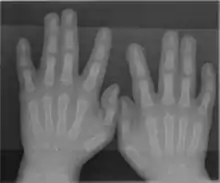

The somatosensory cortex representation of the hand is a dynamic reflection of the fingers on the external hand: in syndactyly people have a clubhand of webbed, shortened fingers. However, not only are the fingers of their hands fused, but the cortical maps of their individual fingers also form a club hand. The fingers can be surgically divided to make a more useful hand. Surgeons did this at the Institute of Reconstructive Plastic Surgery in New York to a 32-year-old man with the initials O. G.. They touched O. G.’s fingers before and after surgery while using MRI brain scans. Before the surgery, the fingers mapped onto his brain were fused close together; afterward, the maps of his individual fingers did indeed separate and take the layout corresponding to a normal hand.[27]

A rare anatomical variation affects 1 in 500 humans, in which the individual has more than the usual number of digits; this is known as polydactyly. A human may also be born without one or more fingers or underdevelopment of some fingers such as symbrachydactyly. Extra fingers can be functional. One individual with seven fingers not only used them but claimed that they "gave him some advantages in playing the piano".[28]